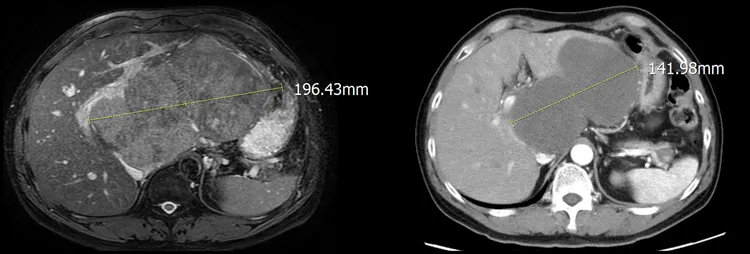

亞洲大學附屬醫院肝膽腸胃科主治醫師許樹湖指出,吳先生是B肝帶原者,長年來幾乎都沒持續追蹤病情,且本身有飲酒習慣,去年8月檢查出左肝長出1個近20公分大的腫瘤,也壓迫到肝門靜脈血管,佔據原本正常的肝臟幾乎75%,大幅增添手術切除的難度,經亞大醫院肝膽腸胃科、放射腫瘤科以及一般外科跨科討論後,決定採取「四箭療法」一拚。

醫師檢查發現,患者左肝腫瘤有近20公分大。亞大醫院提供

放腫科主任王博民說,所謂「四箭療法」是指一般肝癌患者會透過標靶藥物先控制病情,考量該患者肝腫瘤過於巨大,決定搭配免疫治療、「好神刀」放射治療及切肝手術等3種合併療法,前三者先讓肝腫瘤在4週密集治療後,迅速從20公分縮小到14公分,達到安全範圍後,再由一般外科團隊接手治療。